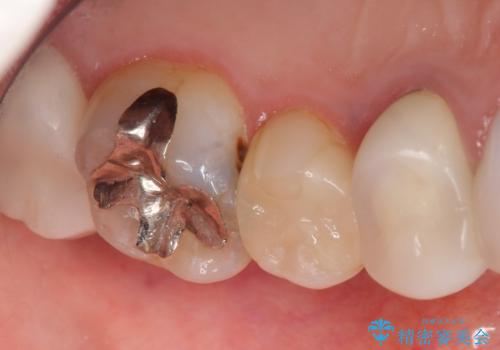

- 奥歯がたまにしみることを主訴に来院された患者様です。

精査したところ、奥歯のメタルインレー(銀の詰め物)の下でう蝕が広がっていました。

う蝕を丁寧に除去したのち、セラミックインレーによる補綴治療を行いました。